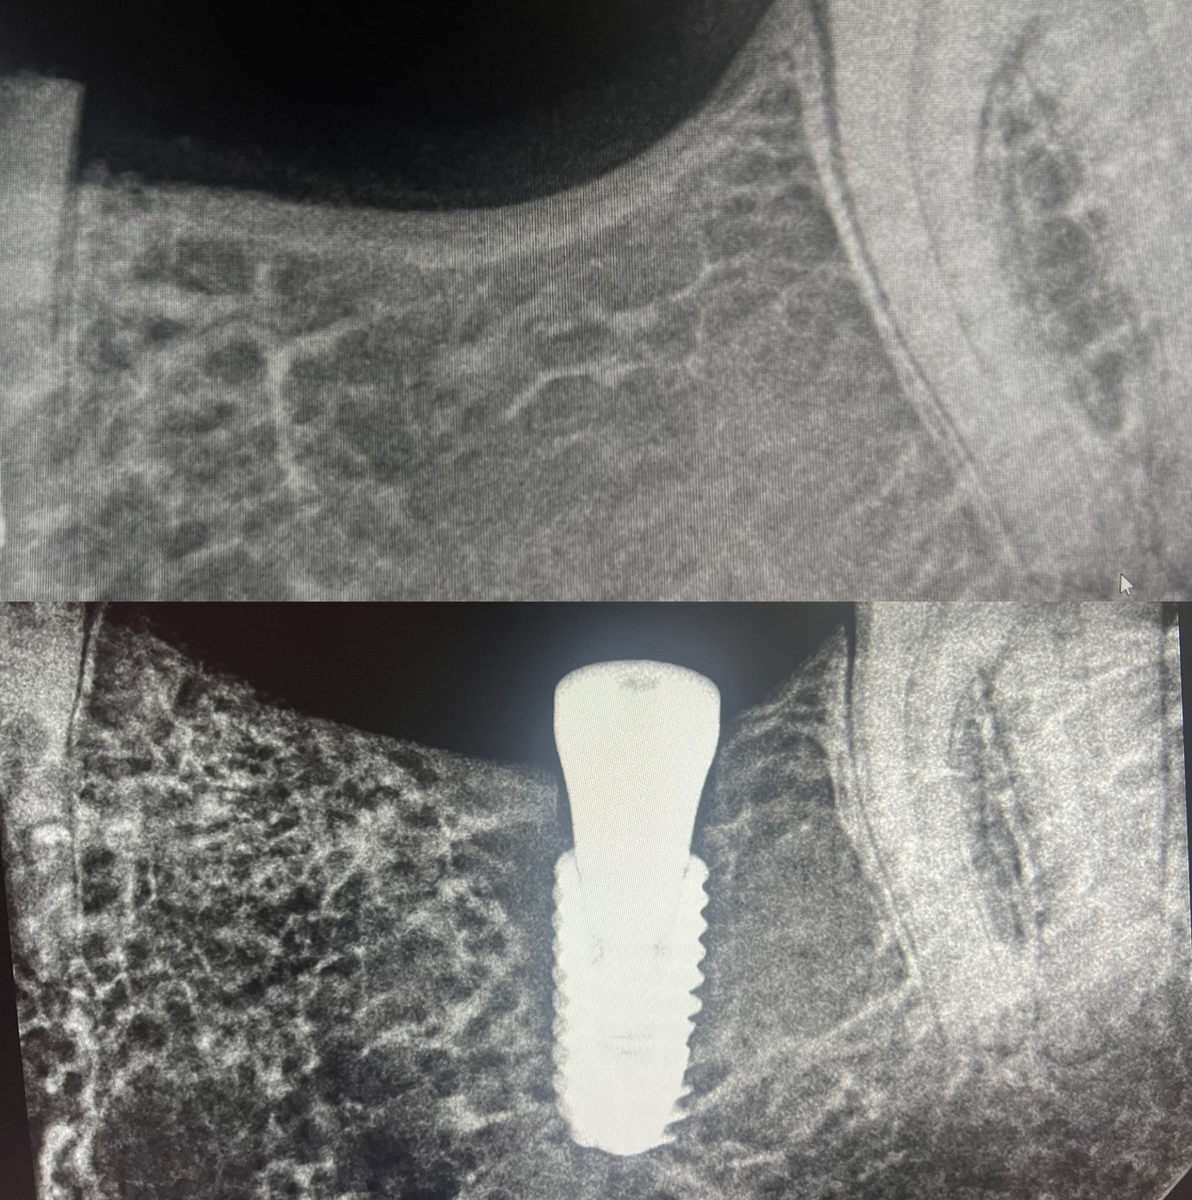

Anterior Implant Single Tooth

✨ Front tooth implant restoration at Grand Oak Dental Care in Antioch! ✨ This patient came to us missing a front tooth and wanted a natural-looking, long-term solution. Our dentist placed a dental implant to replace the missing tooth, and once healing was complete, we removed the healing abutment and took a precise digital impression. Using advanced digital dentistry, we fabricated a custom abutment and bonded a translucent, esthetic zirconia implant crown to perfectly match the surrounding teeth. The result is a strong, natural-looking restoration that blends seamlessly with the smile and restores confidence. If you're missing a front tooth and want a permanent, beautiful solution, our dentist in Antioch can help. Contact Grand Oak Dental Care today to schedule your consultation!